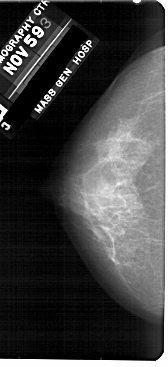

A_1907_1.RIGHT_MLO

RIGHT_MLO LINES 5101 PIXELS_PER_LINE 2566 BITS_PER_PIXEL 12 RESOLUTION 43.5 OVERLAY

FILE: A_1907_1.RIGHT_MLO.OVERLAY

TOTAL_ABNORMALITIES 1

ABNORMALITY 1

LESION_TYPE CALCIFICATION TYPE PLEOMORPHIC DISTRIBUTION CLUSTERED

ASSESSMENT 4

SUBTLETY 2

PATHOLOGY MALIGNANT